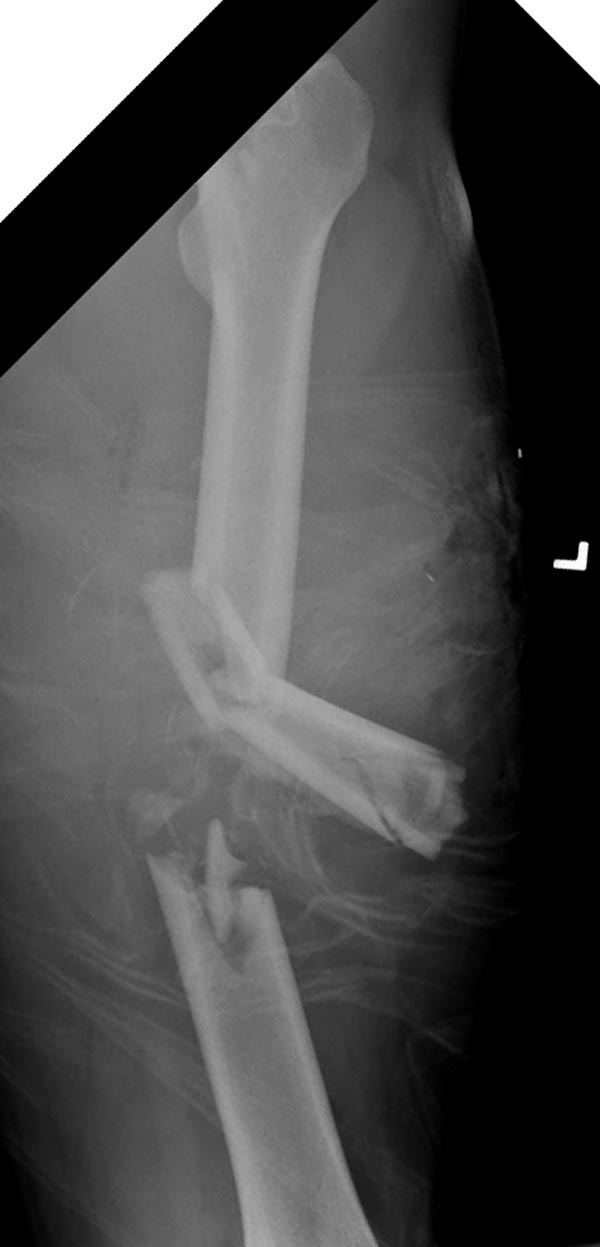

Здесь выставлен ренгенограммы больного, ему 21, травму получил в результате высокоскоростной погони на украденной машине, которая закончилась смертью трех остальных “боевых комрадов”. Начатую коллегой открытую операцию на шейке пришлось закончить мне, установкой винтов и ретроградной фиксацией бедра. Выписка в обычное сроки и наблюдался амбулаторно. Каждый раз напоминали о возможности осложнений ввиде несращения! По истечению 4 месяцев появились признаки варусной деформации. На СТ срезах несращение шейки и бедра. Риминг, замена на более толстый гвоздь и вальгусная остеотомия.

Сразу скажу, что пациент вчера (8.04) прооперирован - артротомия, остеосинтез мыщелков большеберцовой кости канюлированными винтами, открытая репозиция отломков бедренной кости, ретроградный БИОС, остеосинтез надколенника (центральных его отломков) спицами с проволочной петлей. Двухкратная попытка закрытой репозиции шейки на операционном столе после синтеза бедра - абсолютно неэффективна. Учитывая продолжительность и травматичность операции, шейка отложена на 2-й этап. Плечо наверное на 3-й (если вообще делать). Снимки постараюсь предоставить, но чуть позже.